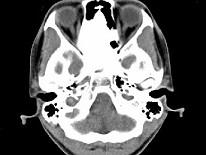

女,17岁,鼻阻塞、头痛两年.如图所示符合筛骨病变最可能的诊断是 ( )

• A.成骨肉瘤

• B.骨瘤

• C.骨化性纤维瘤

• D.软骨瘤

• E.纤维异常增殖症

答案: C